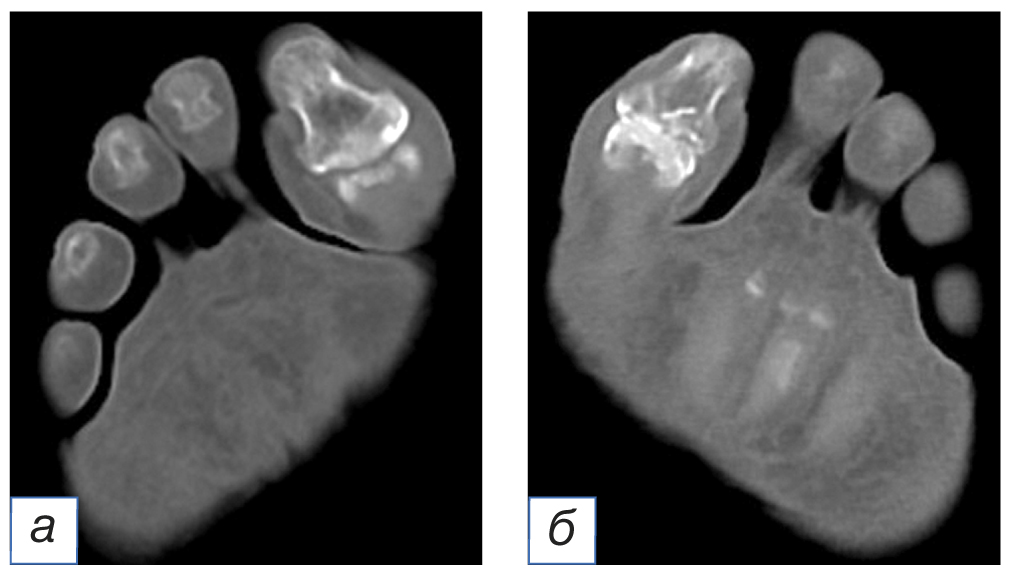

Через 7 месяцев после первичного обращения на амбулаторный приём наблюдалось значительное улучшение внешнего вида раны (рис. 7, а). Полное закрытие открытого костного фрагмента наблюдалось через 12 месяцев от начала лечения в амбулаторных условиях (рис. 7, б–г). На момент полной эпителизации раны рубцовая ткань над дефектом плотная, рубец малоподвижен, подкожно-жировой слой отсутствует. Рубец втянут. Пациентка наблюдается в динамике в течение 2 лет — каждые 3 месяца. За весь период наблюдения рецидивов не наблюдалось. Компьютерная томография стоп по окончании лечения демонстрирует эффективное восстановление костных и мягкотканных структур (рис. 8). Пациентка использует левую стопу в локомоции без каких-либо ограничений.

Рис. 8. Компьютерная томография (а) правой (здоровая) и (б) левой (поражённая) стоп после проведённого лечения

Fig. 8. Computed tomography (а) of the right foot (healthy) and (б) left foot (affected), after the treatment